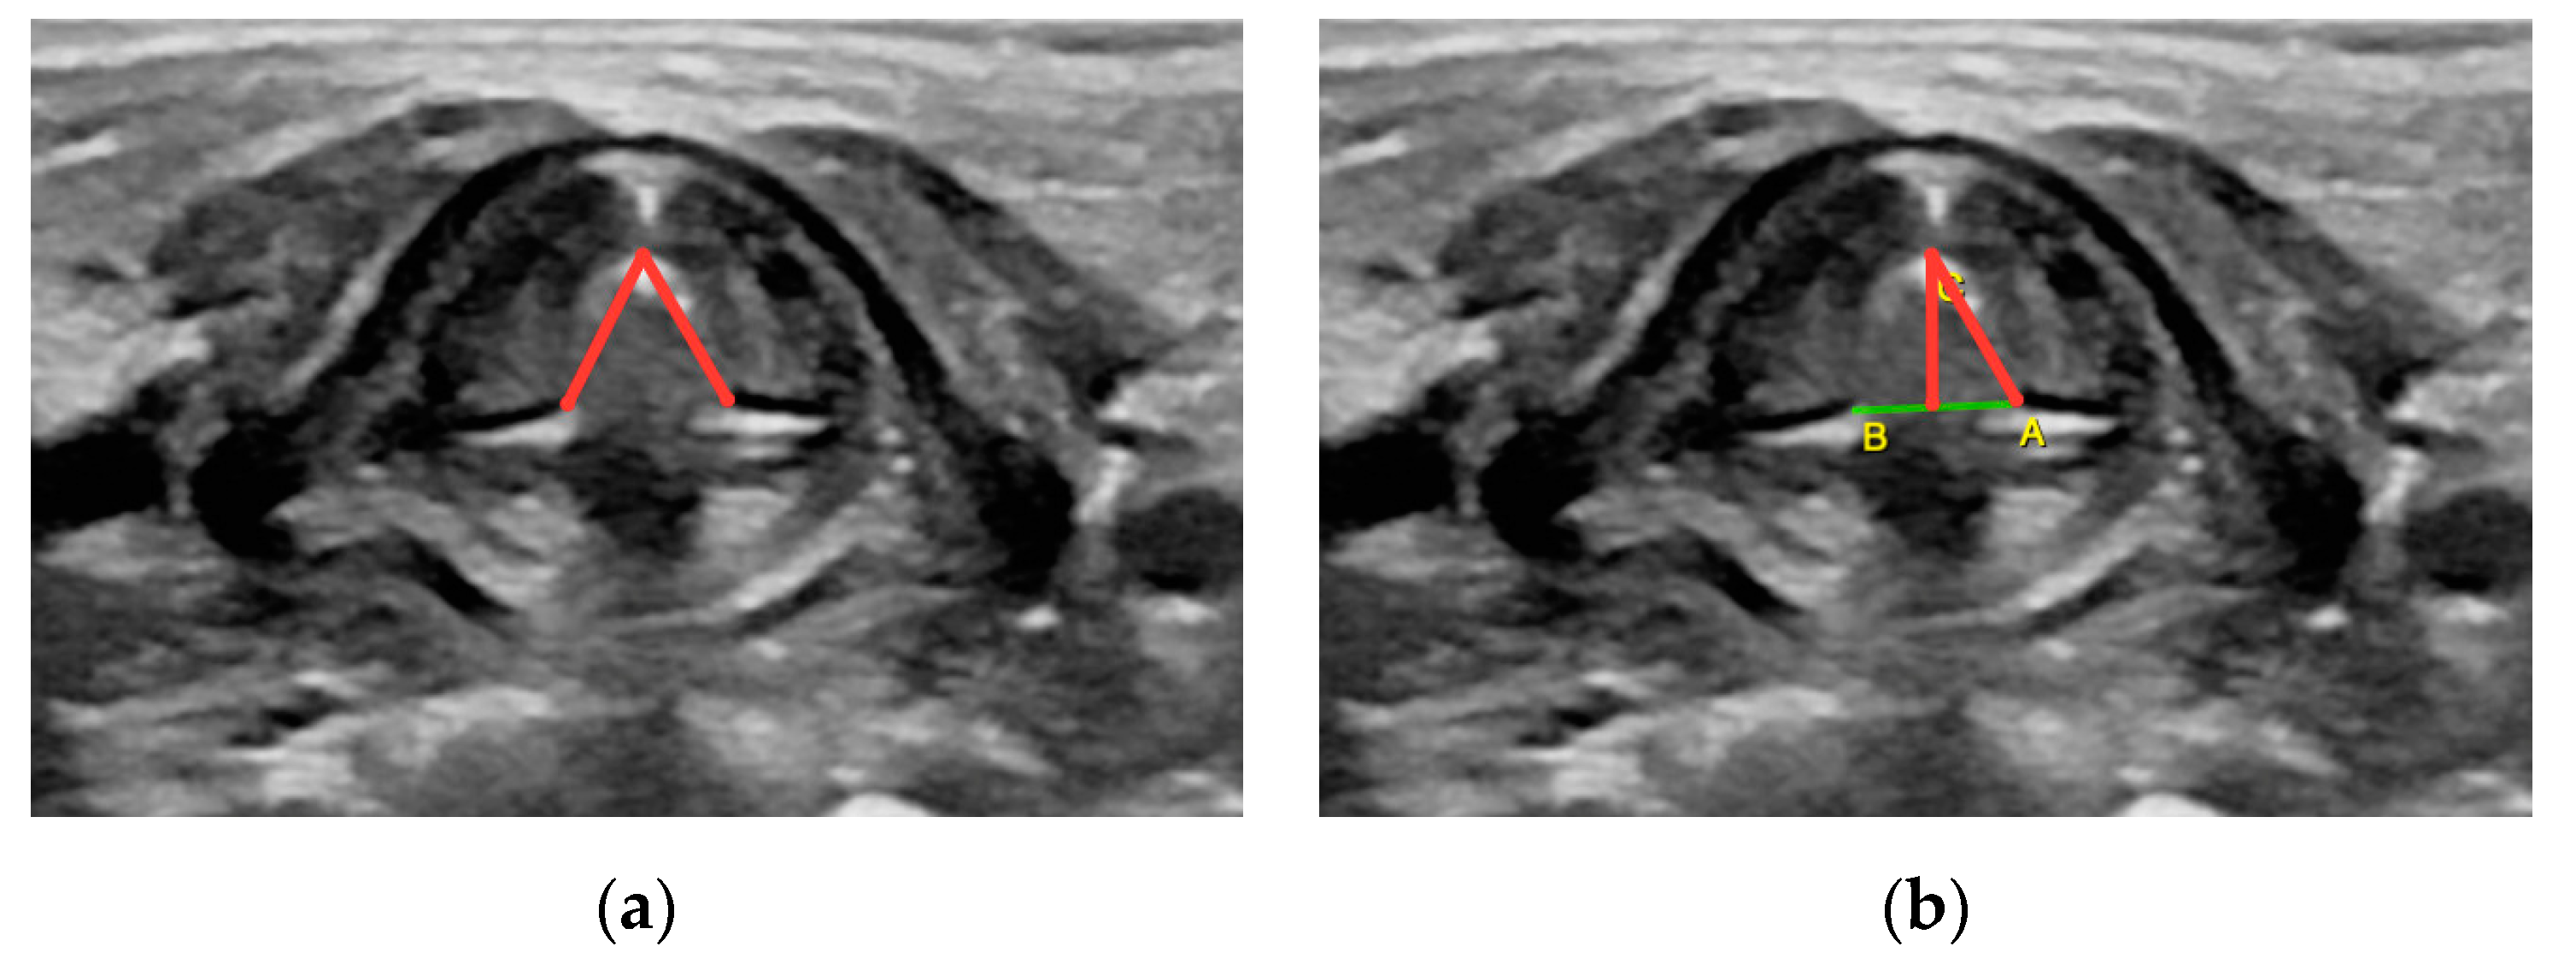

- Angle formed by the vocal cords during calm breathing, considering the opening angle of individual chords (measurement taken in the transverse plane with a line drawn from posterior part of the anterior commissure to the medial margins of the arytenoid gland) (Figure A6);